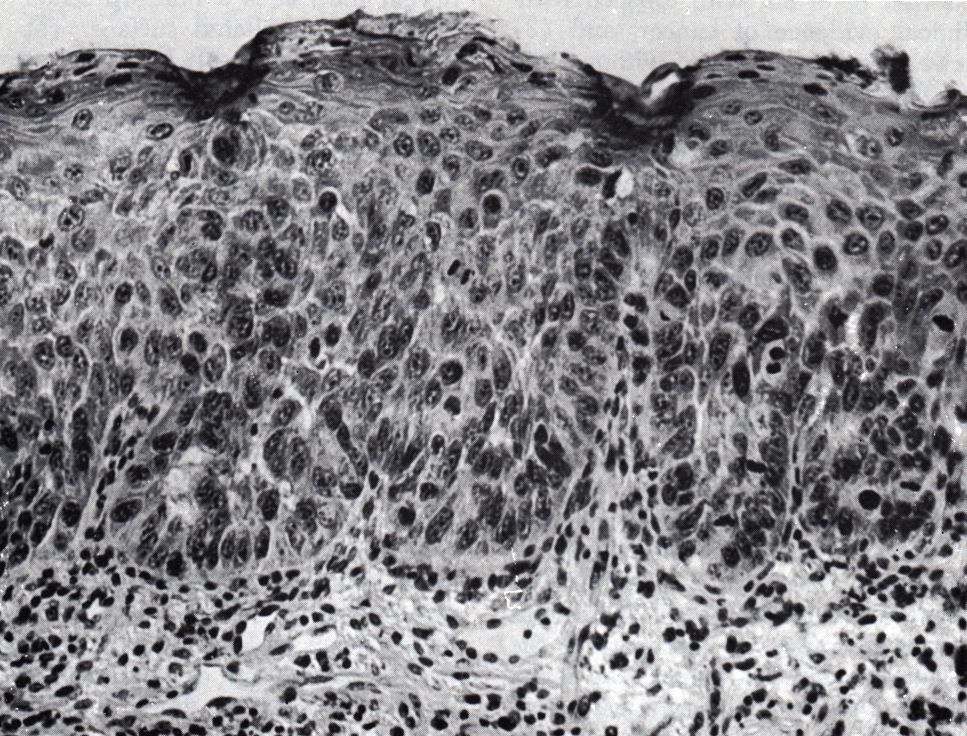

Morphologie |

90% Plattenepithelkarzinome. Seltener basaloid-squamöse Karzinome, lymphoepitheliale Tumoren, Adenokarzinome u.a. | |||||||||||||||

Carcinoma in situ. Auflösung der normalen Schichtung der Epidermis. Zahlreiche Mitosefiguren. Basalmembran noch intakt.![]() | ||||||||||||||||